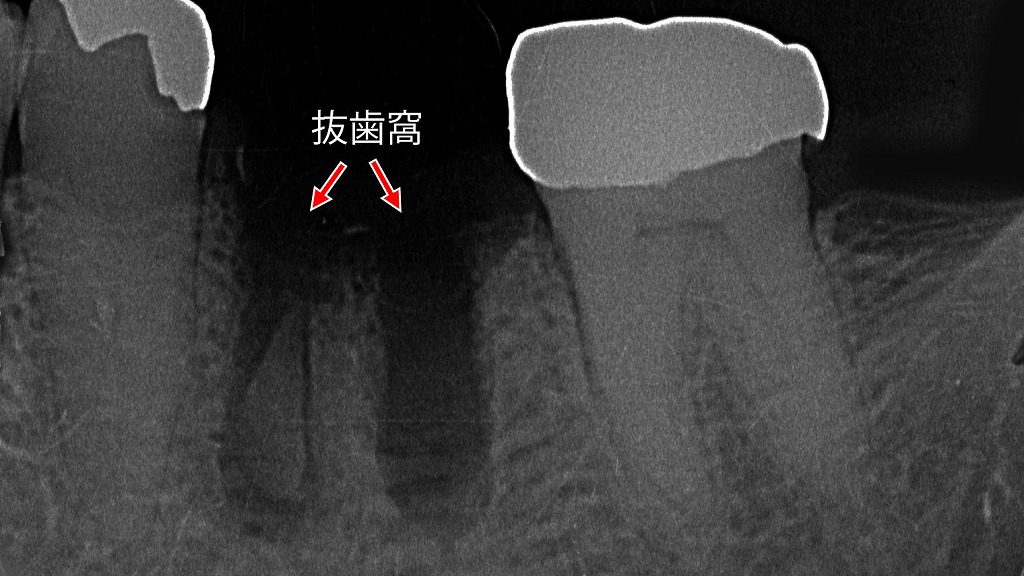

🔍視診で気づける主な特徴

- 抜歯窩が大きく開いている

→ 通常は血餅でふさがる部分が、ぽっかりと開いた状態になっています。 - 抜歯部位が白っぽく見える

→ 血餅がなくなり、骨が露出して白く見えるのが典型的です。 - 黒や赤ではなく白色の抜歯窩

→ 正常なら赤黒い血餅が見えるはずですが、白色は異常のサインです。 - 穴が乾燥し、悪臭や汚れがある

→ 食べかすや細菌によって腐敗臭がすることもあります。